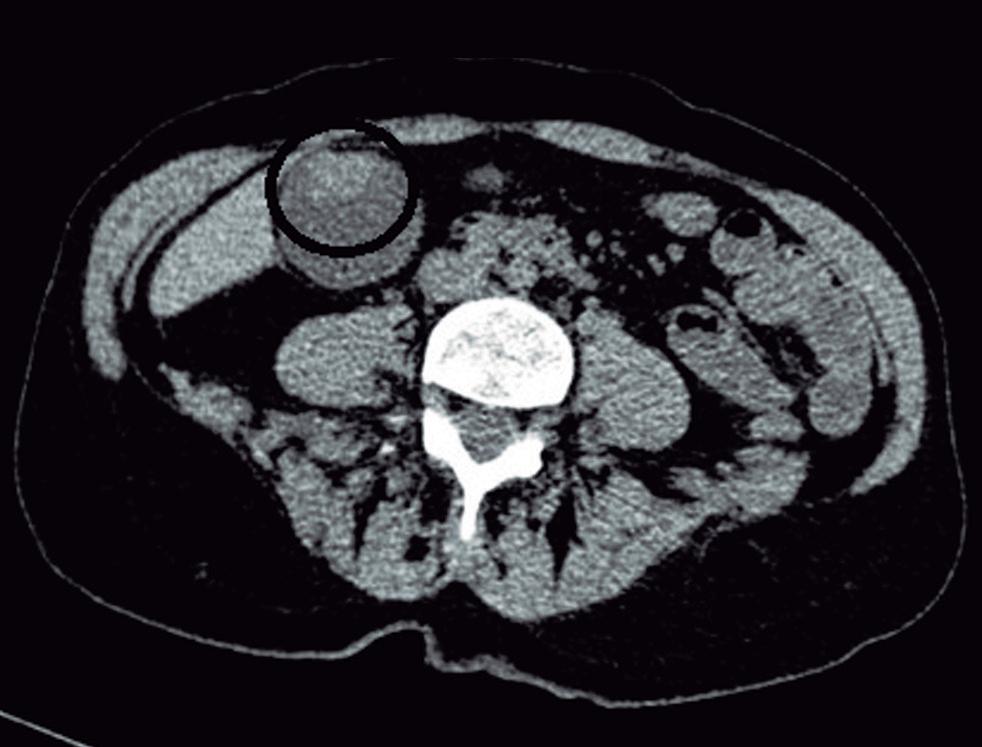

En la TC los hemangiomas son lesiones de bordes netos y frecuentemente de contornos lobulados. Al estar compuestas por vasos, su densidad es igual a la del pool sanguíneo, tanto en las imágenes sin contraste como en las diferentes fases de la evaluación poscontraste. El refuerzo es típicamente globular y progresivo, de forma centrípeta.

19 Acta Gastroenterol Latinoam 2023;53(1):18-27

(Figura 1) En los hemangiomas de mayor tamaño el pasaje del contraste al centro de la lesión toma más tiempo e incluso no ocurre en aquellos más voluminosos.

A, en fase arterial; B, y en fase de equilibrio; C, que muestran una lesión de contornos lobulados y bordes netos en el lóbulo hepático derecho que presenta refuerzo globular, progresivo e isodenso con las estructuras vasculares.

Lesiones benignas localizadas en el hígado desde la mirada de las imágenes Mariano Volpacchio Figura 1. Hemangioma en tomografía computada. Imágenes axiales de la TC sin contraste Figura 2. Hemangioma en la RM. Imágenes axiales de la RM en secuencia T2 con supresión grasa con el refuerzo similar a las estructuras vasculares de aspecto globular y progresivo en sucesivas fases. Nótese la heterogeneidad del hemangioma de mayor tamaño en segmento VI. A B C